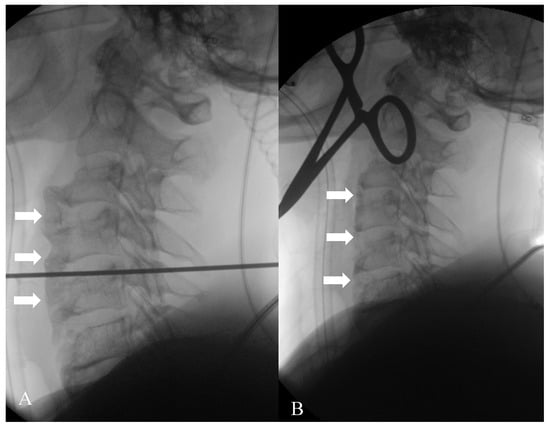

Figure 2. Dynamic swallowing study (Konica Minolta, AeroDR TX, Konica Minolta Inc., Tokyo, Japan) during the administration of 30 mL barium and water in the laterolateral view. The distance between the tube and detector was set at 120 cm. Acquisition parameters: tube voltage, 60 kV; tube current, 80 mA; 15 fps, according to a previous study []; with acquisition time of 28 sec. The huge osteophyte of C3, associated with the coarse calcification of the anterior ligament, results in a narrowing of the pharyngeal lumen (arrow).

Figure 6. Given the severity of the symptoms, the patient underwent a surgical resection of the anterior ligament calcification and osteophytes. (A) represents the beginning of the surgical procedure, with evidence of multiple osteophytes and anterior ligament calcifications (arrows); (B) is the image acquired at the end of the intervention, where they are no longer recognizable (arrows).